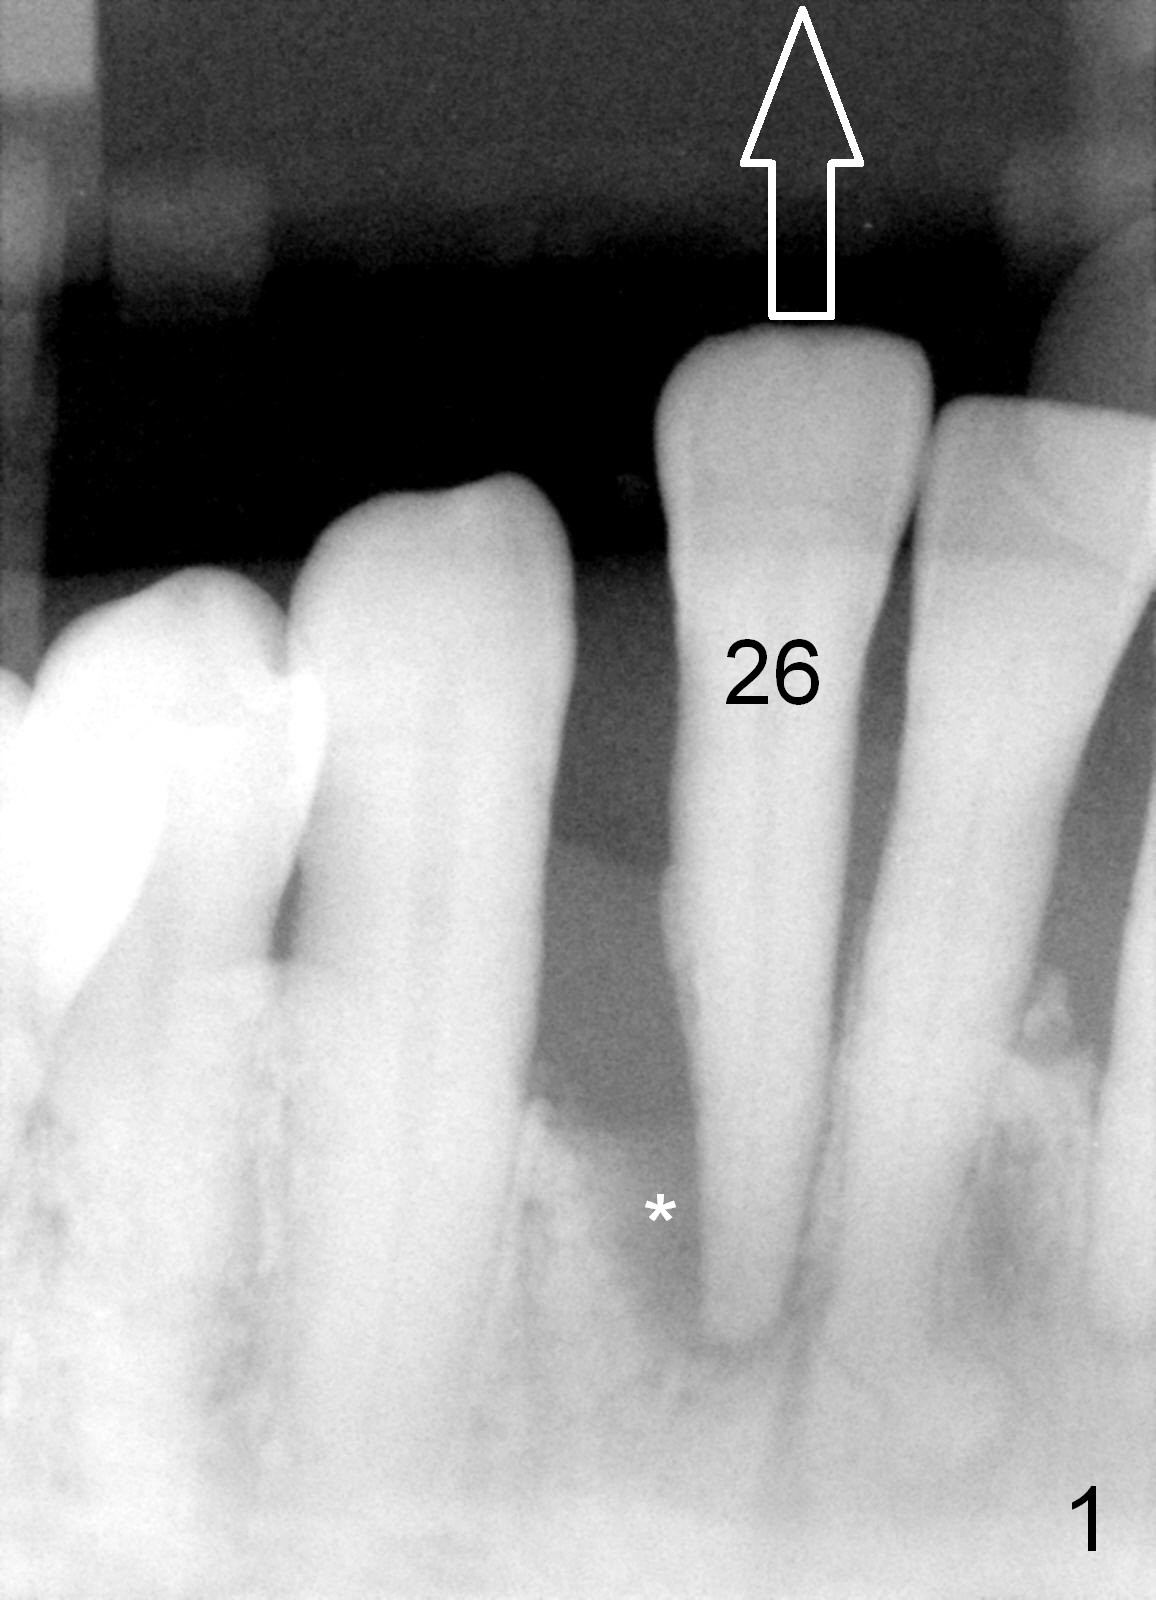

A 65-year-old lady has history of poliomyelitis and use of injection osteoporosis medicine. The tooth #26 is periodontally affected (Fig.1). Since the sensor is not placed deep enough (or there is plenty space above (Fig.1 arrow)), it is difficult to design implant treatment plan (Fig.2). PA has to be taken immediately pre-operatively for precise design.

A tentative design is as follows: a bone-level implant is placed 4 mm subgingival (Fig.3, total gingival height 6 mm (Fig.2)). The cuff will be 4 mm. The most coronal threads are covered by bone graft (red circles).

The length of the implant will be 12 or 14 mm according to the new PA. Is 2.5 mm 1 piece implant indicated for this case? Return to Professionals, Lower Incisor Immediate Implant, Systemic Disease Xin Wei, DDS, PhD, MS 1st edition 03/09/2015, last revision 05/30/2018